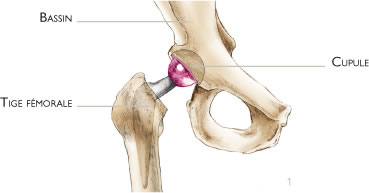

La prothèse totale de hanche est constituée de deux pièces : la cupule qui est une partie hémisphérique creuse implantée au cotyle, et la tige fémorale avec une bille qui est implantée au fémur. La bille remplace la tête du fémur et s’articule avec la cupule (figure 1).